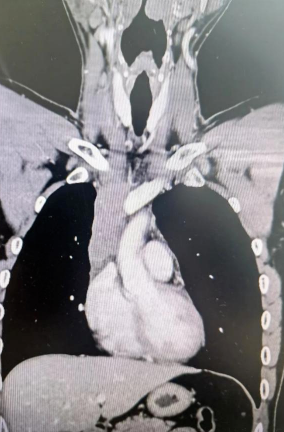

經(jīng)檢查發(fā)現(xiàn)患者前上縱隔腫瘤已經(jīng)完全侵犯了我們?nèi)梭w最主要的大靜脈之一——上腔靜脈,導(dǎo)致上腔靜脈回流嚴(yán)重受阻并導(dǎo)致由上腔靜脈起至左側(cè)無名靜脈、右側(cè)鎖骨下靜脈、右側(cè)頸內(nèi)靜脈等多根自上往下回流的靜脈阻塞,從而形成了廣泛的栓子,牢牢堵住了要流回心臟的血流,只能靠別的一些側(cè)支循環(huán)超負(fù)荷的工作,這也就是為什么孫先生脖子甚至是頭都明顯腫起來的原因。

4月30日,麻醉完成后,縱劈胸骨顯露右上縱隔腫瘤,發(fā)現(xiàn)腫瘤侵入上腔靜脈起始部,右鎖骨下靜脈及右頸內(nèi)靜脈血栓形成并向遠(yuǎn)端延伸。劉志主任團隊將切口向右頸部延長,顯露右側(cè)頸內(nèi)靜脈至下頜角水平。張金洲副院長團隊經(jīng)股動靜脈和左無名靜脈建立體外循環(huán)。在阻斷左無名靜脈遠(yuǎn)端后,李文海副院長團隊完整切除縱隔腫瘤及部分上腔靜脈、左無名靜脈、右鎖骨下靜脈和右頸內(nèi)靜脈切除。張金洲副院長團隊實施了無名靜脈近端、右鎖骨下靜脈和右頸內(nèi)靜脈內(nèi)血栓取出術(shù),并完成了左無名靜脈、右頸內(nèi)靜脈和右鎖骨下靜脈的人工血管置換手術(shù)。歷時6小時,三個外科團隊在麻醉科柴偉主任團隊、體外循環(huán)團隊以及食管超聲和手術(shù)室協(xié)作下,手術(shù)獲得成功。

術(shù)后患者經(jīng)過心外監(jiān)護室和胸外監(jiān)護室的接力治療,目前患者恢復(fù)順利,顏面部腫消失。復(fù)查增強CT三條人工血管通暢。